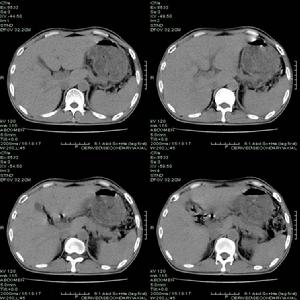

2.腎癌(又稱腎細胞癌、腎透明細胞癌) 注意發病年齡及有無下述表現:①間歇性無痛性血尿、腎區鈍痛,並可出現全身症狀,包括低熱、貧血、紅細胞增多、高血壓、高鈣血症等。②腎區叩擊痛,腎腫大,症狀性精索靜脈曲張及腹部腫物。③泌尿系X線平片及尿路造影:患腎影增大,腎盂、腎盞受壓變形。膀胱鏡檢查可見患側輸尿管開口噴血。④放射性核素腎掃描:癌腫>3cm者出現放射性稀疏區。⑤腎動脈造影(對早期癌更具有診斷價值):顯示出癌瘤的病理血管像,如向腎動脈內注入腎上腺素後再作選擇性腎動脈造影,則病理血管像顯示更為清晰;⑥B超和CT檢查:對腎癌有較高的早期診斷價值。

腎腫瘤3.腎盂癌 注意發病年齡及有無下列臨床表現:①早期即出現眼觀血尿,腎絞痛及腎積水。②靜脈尿路造影:顯示腎盂不規則充盈缺損,腎盞、腎盂積水,輸尿管種植癌,必要時行腎動脈造影以助診斷。③膀胱鏡檢查:輸尿管口噴血,或見種植癌。④尿內可查到癌細胞;⑤B超和CT檢查。

4.腎母細胞瘤(胚胎瘤) 注意發病年齡(大多發生在幼兒,偶見於中青年)及有無下述表現:①以腹部腫物為第一症狀,貧血、低熱、高血壓常見,但血尿少見。②尿路造影不顯影或顯示腎盂、腎盞變形移位,腎影增大,腫瘤區可見鈣化影,輸尿管可被腫瘤推向中線。③放射性核素腎掃描,顯示患腎放射性缺損及稀疏。④肺、骨骼可有早期轉移。⑤B超、CT或MRI檢查。